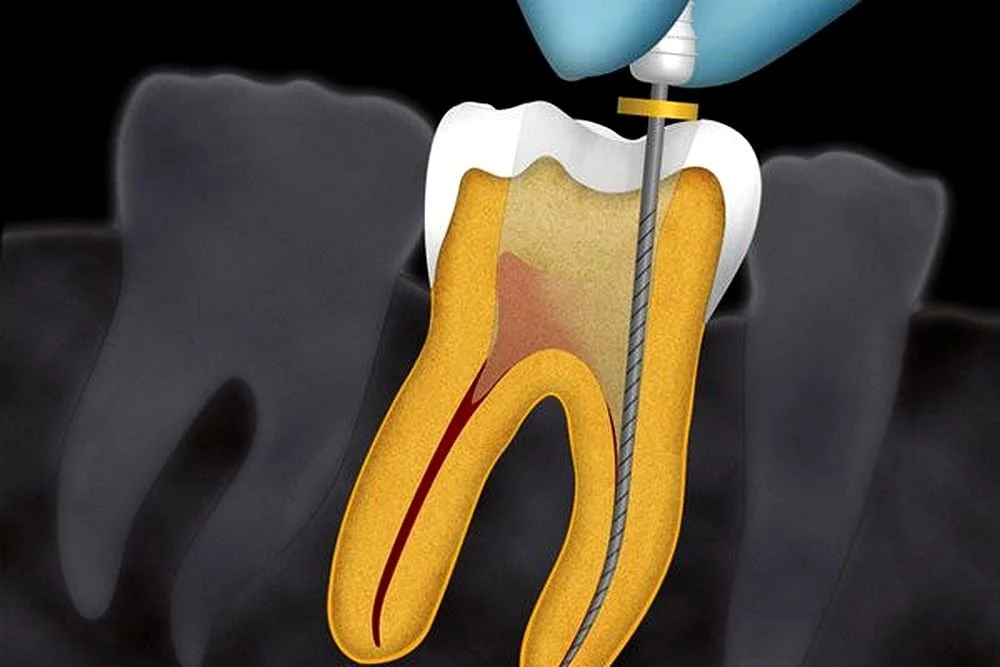

Endodontic Treatment

Our endodontic procedures remove infected pulp tissue, disinfect the root canals, and seal the tooth to prevent further infection—preserving your natural tooth and relieving pain.